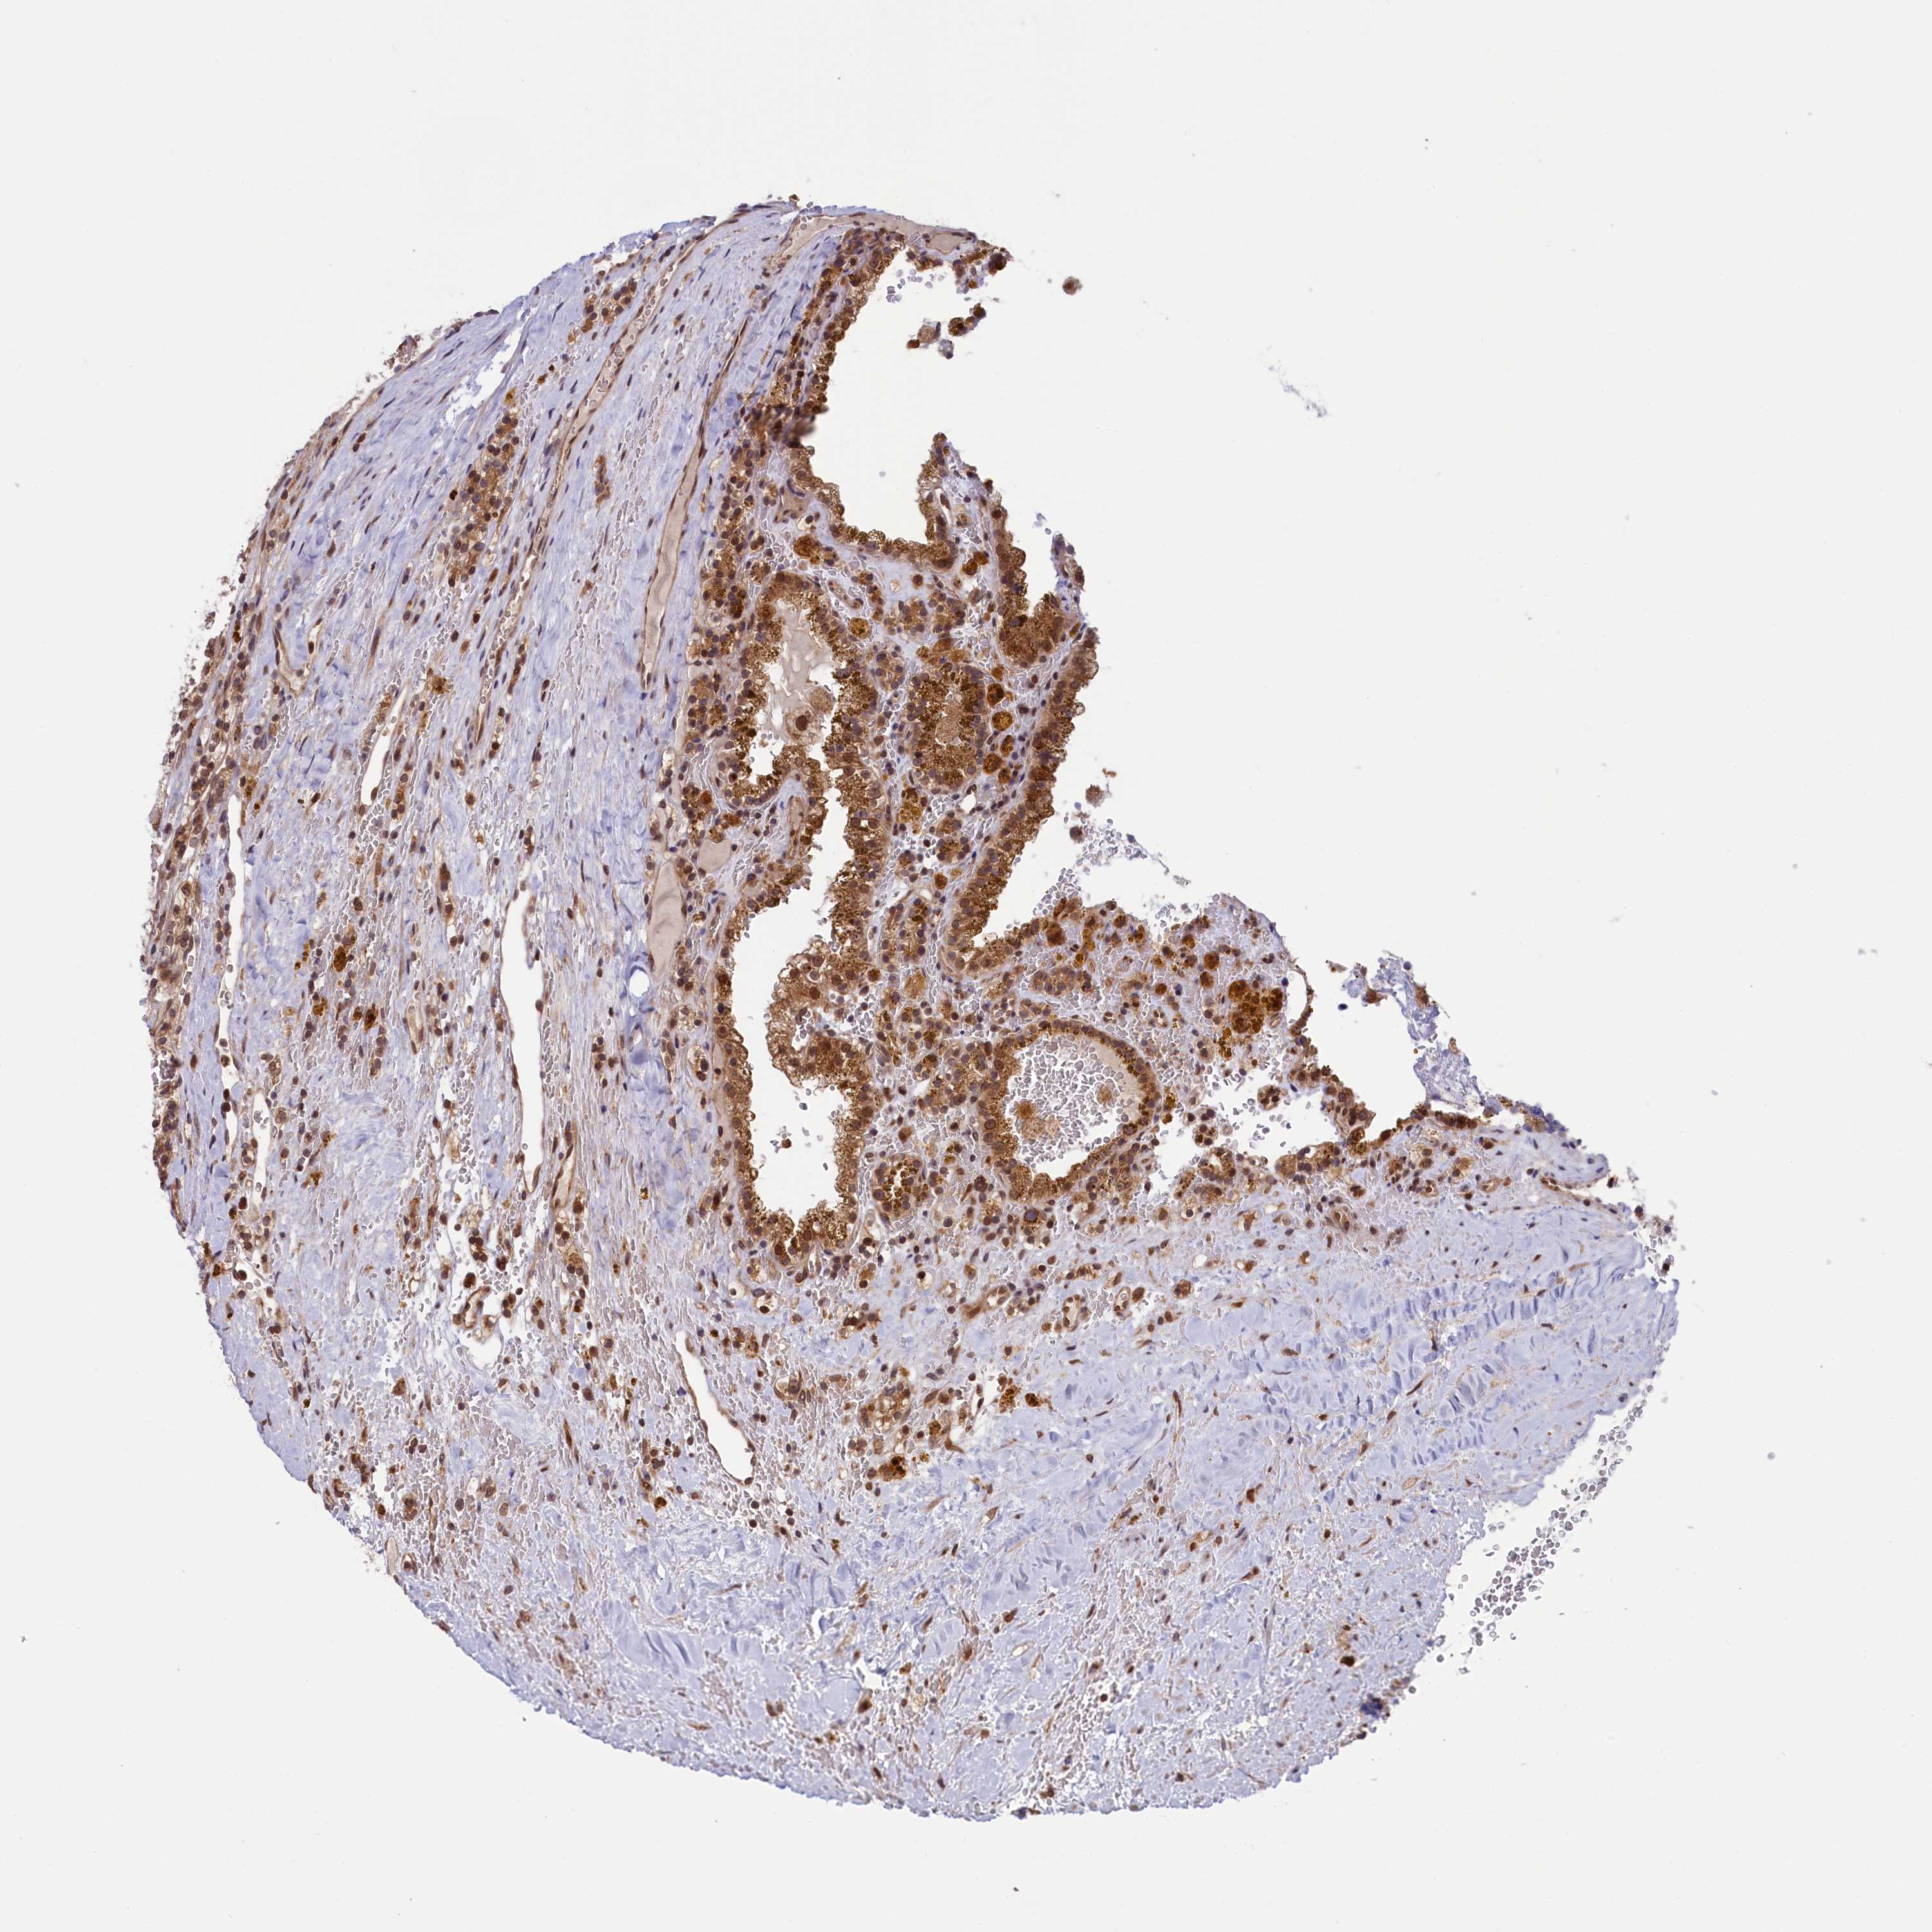

KIDNEY RENAL CLEAR CELL CARCINOMA (VALIDATION) - Interactive survival scatter ploti

The Survival Scatter plot shows the clinical status (i.e. dead or alive) for all individuals in the patient cohort, based on the same data that underlies the corresponding Kaplan-Meier plots. Patients that are alive at last time for follow-up are shown in blue and patients who have died during the study are shown in red.

The x-axis shows the expression levels (FPKM) of the investigated gene in the tumor tissue at the time of diagnosis. The y-axis shows the follow-up time after diagnosis (years). Both axes are complimented with kernel density curves demonstrating the data density over the axes. The top density plot shows the expression levels (FPKM) distribution among dead (red) and alive patients (blue). The right density plot shows the data density of the survived years of dead patients with high and low expression levels respectively, stratified using the cutoff indicated by the vertical dashed line through the Survival Scatter plot. This cutoff is automatically defined based on the FPKM cutoff that minimizes the p-score. The cutoff can be changed by dragging the vertical line or by entering a cutoff value in the square labeled "Current cut-off".

Under the Survival Scatter plot the p-score landscape (black curve; left axis) is shown together with dead median separation (red curve; right axis). Dead median separation is the difference in median mRNA expression between patients who have died with high and low expression, respectively. It is calculated as follows: median FPKM expression of dead patients with high expression - median FPKM expression of dead patients with low expression. This is intended to aid the user in visually exploring custom cutoffs and the associated p-scores and dead median separation.

Individual patient data is displayed and can be filtered by clicking on one or more of the category buttons on the top of the page. Categories describing expression level and patient information include: high, low, alive, dead, female, male and tumor stages. The scale of the x-axis can be toggled between linear and log-scale by clicking on the "x log" button. Mouse-over function shows TCGA ID, patient information and mRNA expression (FPKM) for each patient.

& Survival analysisi

Kaplan-Meier plots summarize results from analysis of correlation between mRNA expression level and patient survival. Patients were divided based on level of expression into one of the two groups "low" (under cut off) or "high" (over cut off). X-axis shows time for survival (years) and y-axis shows the probability of survival, where 1.0 corresponds to 100 percent.

NAE1 is not prognostic in Kidney Renal Clear Cell Carcinoma (validation)

: 28.09

Average pTPM 36.0

Number of samples 100